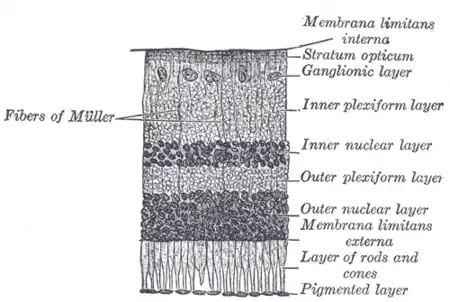

Retinal layers

The vertebrate retina has 10 distinct layers.[15] From closest to farthest from the vitreous body:

- Inner limiting membrane – basement membrane elaborated by Müller cells

- Nerve fibre layer – axons of the ganglion cell bodies (a thin layer of Müller cell footplates exists between this layer and the inner limiting membrane)

- Ganglion cell layer – contains nuclei of ganglion cells, the axons of which become the optic nerve fibres, and some displaced amacrine cells[2]

- Inner plexiform layer – contains the synapse between the bipolar cell axons and the dendrites of the ganglion and amacrine cells[2]

- Inner nuclear layer – contains the nuclei and surrounding cell bodies (perikarya) of the amacrine cells, bipolar cells, and horizontal cells[2]

- Outer plexiform layer – projections of rods and cones ending in the rod spherule and cone pedicle, respectively, these make synapses with dendrites of bipolar cells and horizontal cells.[2] In the macular region, this is known as the Fiber layer of Henle.

- Outer nuclear layer – cell bodies of rods and cones

- External limiting membrane – layer that separates the inner segment portions of the photoreceptors from their cell nuclei

- Inner segment / outer segment layer – inner segments and outer segments of rods and cones, the outer segments contain a highly specialized light-sensing apparatus.[16][17]

- Retinal pigment epithelium – single layer of cuboidal epithelial cells (with extrusions not shown in diagram). This layer is closest to the choroid, and provides nourishment and supportive functions to the neural retina, The black pigment melanin in the pigment layer prevents light reflection throughout the globe of the eyeball; this is extremely important for clear vision.[18][19][20]

These layers can be grouped into four main processing stages—photoreception; transmission to bipolar cells; transmission to ganglion cells, which also contain photoreceptors, the photosensitive ganglion cells; and transmission along the optic nerve. At each synaptic stage, horizontal and amacrine cells also are laterally connected.

In section, the retina is no more than 0.5 mm thick. It has three layers of nerve cells and two of synapses, including the unique ribbon synapse. The optic nerve carries the ganglion-cell axons to the brain, and the blood vessels that supply the retina. The ganglion cells lie innermost in the eye while the photoreceptive cells lie beyond. Because of this counter-intuitive arrangement, light must first pass through and around the ganglion cells and through the thickness of the retina, (including its capillary vessels, not shown) before reaching the rods and cones. Light is absorbed by the retinal pigment epithelium or the choroid (both of which are opaque).

Between the ganglion-cell layer and the rods and cones are two layers of neuropils, where synaptic contacts are made. The neuropil layers are the outer plexiform layer and the inner plexiform layer. In the outer neuropil layer, the rods and cones connect to the vertically running bipolar cells, and the horizontally oriented horizontal cells connect to ganglion cells.